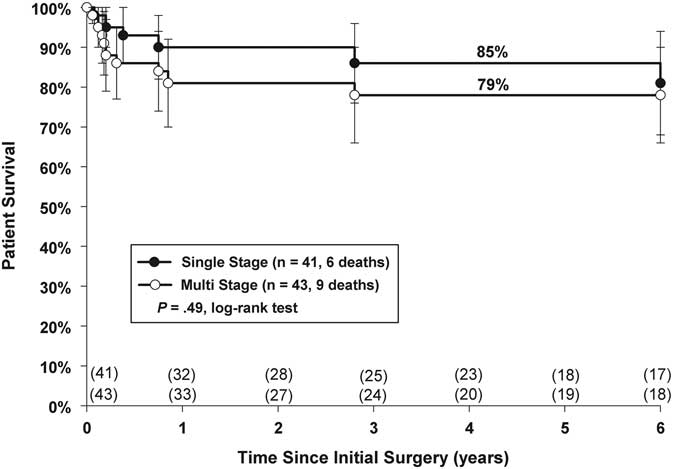

Overall mortality was 6 (15%) versus 9 (21%) for Groups 1 and 2, respectively. A period of 5-year actuarial survival was similar (Group 1: 85%; Group 2: 79%, p = 0.49 (Fig 2)). In Group 1, two deaths occurred within 30 days, two died within 1 year, and the remaining two deaths occurred at 2.8 and 6.8 years post unifocalisation, respectively. In Group 2, four patients died in-hospital, another four died within 1 year of initial unifocalisation, and one patient died 2.9 years after initial unifocalisation.

Figure 2 Kaplan–Meier actuarial survival analysis of single-versus multi-stage repair.